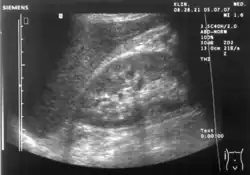

Ultrasonographic view of the abdomen demonstrating fluid within Morison's pouch

Since it is a potential space, the hepatorenal recess is not normally filled with fluid. However, this space becomes significant in conditions in which fluid collects within the abdomen (most commonly ascites and hemoperitoneum). The intraperitoneal fluid, be it blood, ascites, or dialysate, collects in this space and may be visualized, most commonly via ultrasound or computed tomography (CT) scanning. As little as 30 or 40 ml of fluid in the abdominal cavity may be visualized in this space.

Early visualization of fluid in the hepatorenal recess on FAST scan may be an indication for urgent laparotomy.[2]